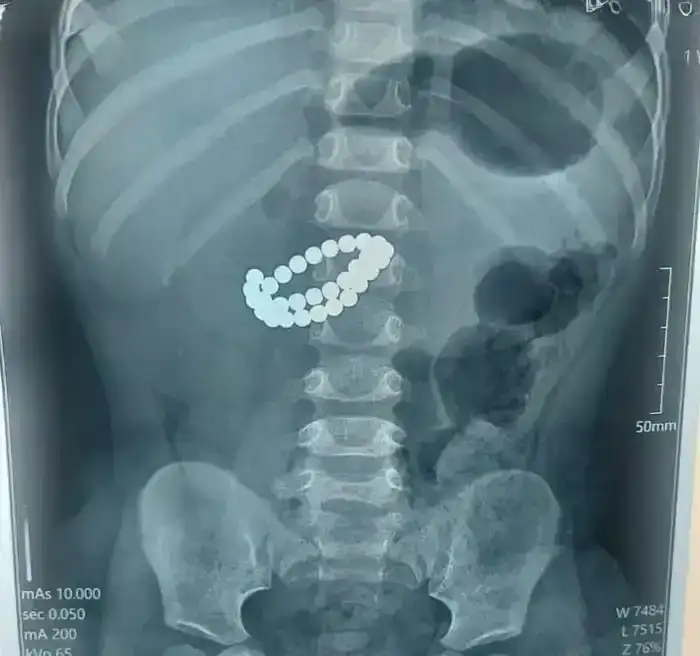

В Алматы произошел случай, который подчеркивает важность бдительности родителей. Врачи Центра детской неотложной медицинской помощи провели экстренную операцию, чтобы спасти малыша, проглотившего 31 магнит. Ребенок, которому всего 1 год и 9 месяцев, поступил в приемное отделение в тяжелом состоянии.

После тщательного обследования врачи установили, что в кишечнике находятся инородные тела — 31 магнит, а также множественные перфорации тонкой кишки и диффузный каловый перитонит. Для спасения жизни ребенка потребовалось срочное хирургическое вмешательство. Врачами была выполнена срединная лапаротомия с ревизией органов брюшной полости.

Хирурги успешно извлекли магниты и ушили перфорации кишечника. Также была проведена санация и дренирование брюшной полости, а кишечник интубирован трансанальным способом. Как отметил хирург Аскар Ризванов, опасность магнитов заключается в том, что, попадая в организм, они могут притягиваться друг к другу.

Это приводит к тому, что стенки кишки зажимаются, нарушается кровообращение, и развивается некроз тканей. Если не принять меры, за короткое время может возникнуть перитонит. Врачи настоятельно рекомендуют родителям быть внимательными и исключить доступ детей к опасным магнитным игрушкам.